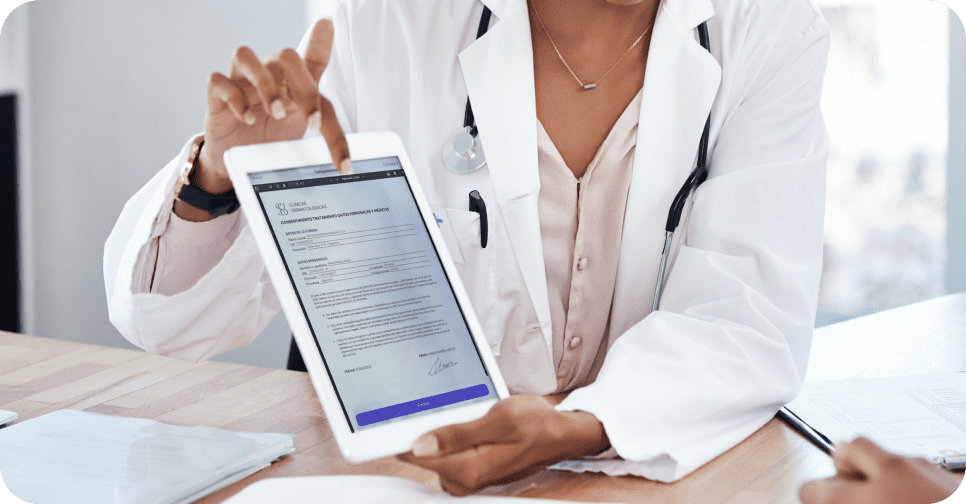

Asegura una gestión eficaz y confiable de tu clínica, garantizando la firma digital de consentimientos médicos y cumpliendo con la Ley de Protección de Datos Personales.

Almacena de manera segura la documentación médica del paciente y lleva un control sobre la trazabilidad de consumibles para preservar la seguridad del paciente.